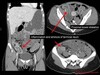

What pathology is seen here? Label A-D

Hepatocellular Carcinoma (HPC) -Multiphase study A: Non contrast: Mass is hypodense B: Arterial phase: Aorta bright, tumour enhanced, non uniform enhancement (mish mash) C: Portal venous phase D: Delayed phase

245